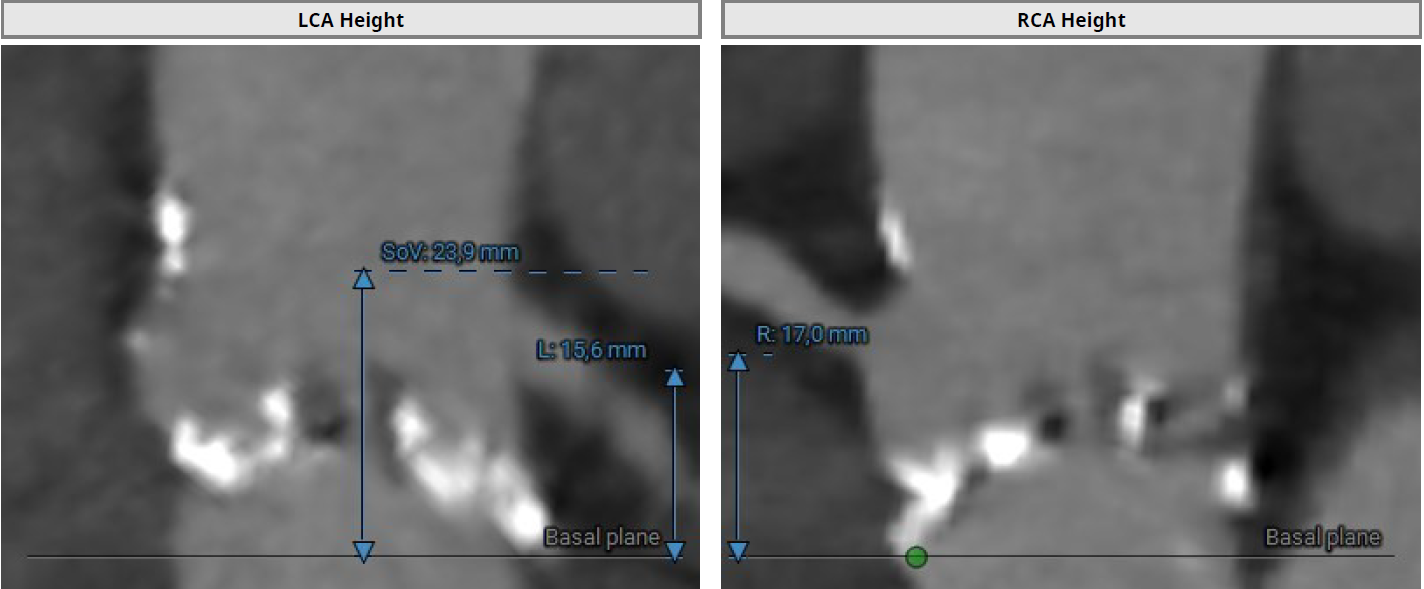

Since 2023 - frequent hospitalizations due to attacks of chest pain, attacks of nocturnal asthma. According to echocardiography - EF-52%. AV leaflet opening 0.5 cm. Prominent calcification of the aortic valve and fibrous ring. V-5.9 m/s, PGmax-140 mmHg, PGmean-88 mmHg, S-0,5 cm2. Aortic regurgitation grade II. Mitral regurgitation grade II-III. No zones of local contractility disturbance. Consulted with a cardiac surgeon, surgical correction of aortic defect was recommended.

The rightsubclavian vein was punctured. A 6F intraducer was inserted. The endocardialelectrode for temporary cardiac stimulation was placed in the right ventricularcavity. The left radial artery was punctured. A 6F intraducer was placed, andan invasive pressure line was connected. The left common femoral artery waspunctured. The 6F intraducer is inserted. Pigtail 6 F diagnostic catheter isinserted into the non-coronary sinus. Puncture of the right common femoralartery was performed. Two intravascular sutures were placed using the Pro Glidepre-stitching technique. The 12F intraducer was placed in the lumen of the rightfemoral artery. The Confida wire wasguided into the left ventricular cavity. Aortic valve valvuloplasty wasperformed using balloon catheters 20.0-40.0 mm, 25.0-40.0 mm. Asystole wasregistered on ECG and resuscitative measures were started. During indirectheart massage, endovascular prosthesis Portico - 29mm was implanted in aorticposition. At the control aortography, the aortic valve prosthesis is optimallyspread out.